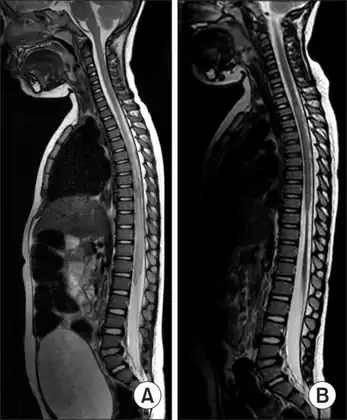

MRI of individual diagnosed with transverse myelitis -

Axial T2 MRI of cervical spine demonstrating normal cord signal (green circle) and increased T2 signal in the central cord (red circle).